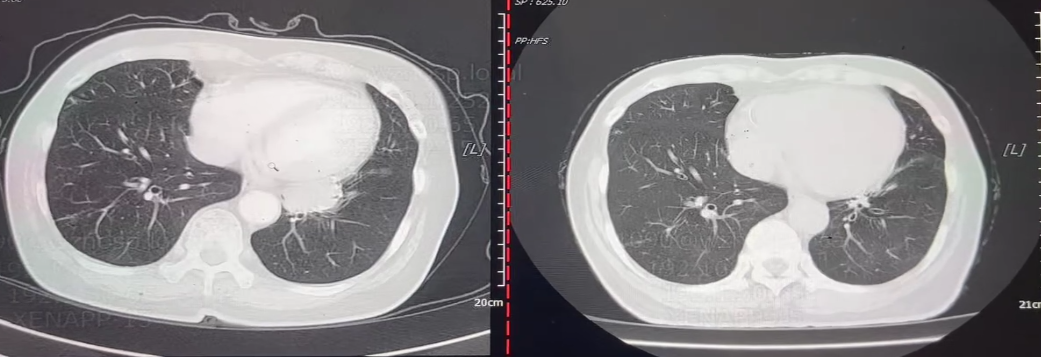

图片4.png

胸部CT(左:2023年11月12日;右:2024年5月24日)

• 2025年7月7日:胸部CT呈现左肺下叶肿瘤治疗后改变,未见明确肿块。对比2025年4月2日CT,病情再次得到有效控制。

• 2025年10月10日:胸部CT显示肺部病灶消失,疗效评估为CR。

图片8.png

胸部CT(左:2025年4月2日;中:2025年7月7日;右:2025年10月10日)